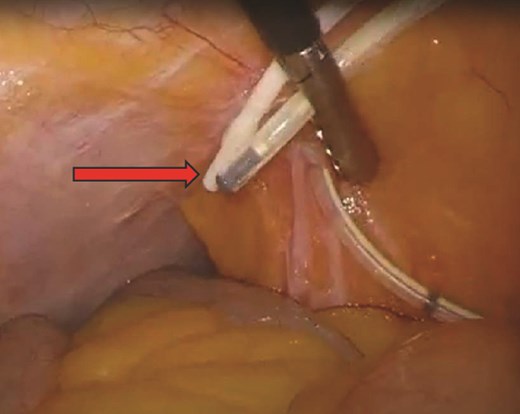

Our patient is a 38-year-old female with a medical history of cerebral palsy, congenital cerebral ventricular dilation and hydrocephalus with VP shunt placement in infancy, sleep apnea and morbid obesity (body mass index (BMI) 43 kg/m2) who underwent laparoscopic Roux-en-Y gastric bypass (LRYGB) and was discharged on postoperative day (POD) #1. On POD#15, she sustained a syncopal event and presented to the emergency department. She was found to be tachycardic to 105 beats/min with epigastric tenderness and a leukocytosis of 15.6 (thou/μL). Computed tomography (CT) scan revealed a 4.8 × 10.1 cm air- and fluid-containing collection worrisome for abscess versus contained small bowel perforation (Fig. 1). She underwent diagnostic laparoscopy converted to exploratory laparotomy, revealing an infected hematoma with abscess in the mesentery of the proximal common channel and adjacent ischemic bowel without evidence of perforation. She underwent drainage of the abscess and resection of the compromised bowel, including her jejunojejunostomy (JJ) and 40 cm of the common channel. A new JJ was created. Intraoperatively, two VP shunt catheters were inspected and consultation from neurosurgery was obtained (Fig. 2). One shunt was determined to be nonfunctional and was removed. The functional shunt was externalized. Postoperatively, she was admitted to the intensive care unit for shunt monitoring, placed on cefepime, metronidazole and vancomycin, and her shunt was serially cultured. Intraabdominal fluid cultures from the operating room were polymicrobial, including Klebsiella oxytoca, Citrobacter freundii complex, Enterococcus faecalis, Parvimonas micra, and Prevotella. After persistently negative shunt cultures and 12 days of intravenous antibiotics, her shunt was re-internalized on POD#14 (POD#28). She completed a 14 day total course of antibiotics and was discharged home. She was most recently seen for an annual visit and is doing well, having lost 33% of her total body weight, and 58% of her excess body weight.